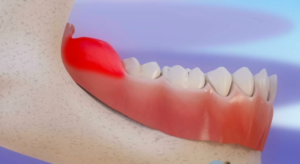

Чаще всего этому заболеванию подвержены десны на нижней челюсти около зуба мудрости.

Воспалительный процесс сопровождается отеком десны, ее покраснением и выраженными болевыми ощущениями и может протекать как в острой, так и в хронической форме.

- отек мягких тканей десны в области растущего зуба, их покраснение;

- Отек и покраснение в области пораженной десны;